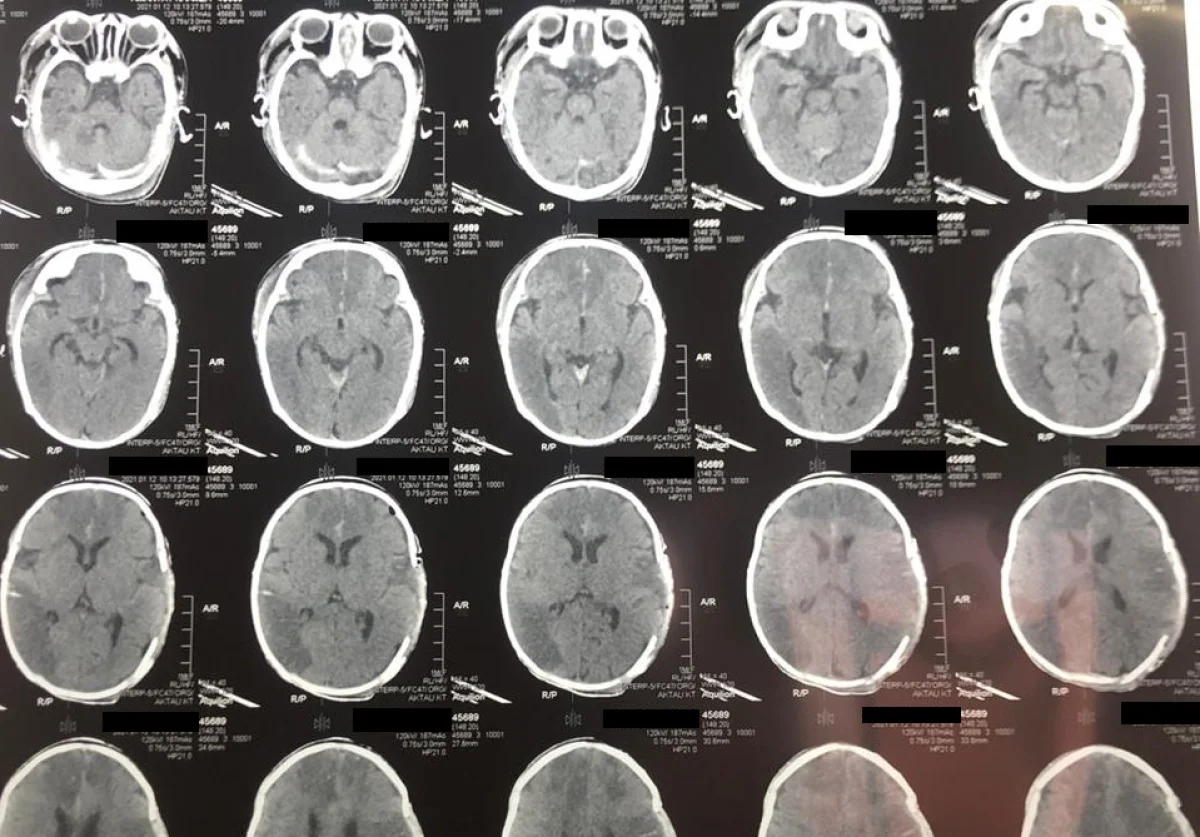

Младенца с инсультом спасли врачи в Мангистау

Врачи спасли жизнь двухмесячного ребенка, у которого случился инсульт. Об этом сообщили в Мангистауской областной многопрофильной детской больнице.

Ребенка с диагнозом «Острое нарушение мозгового кровообращения» (инсульт новорожденных) доставили в Мангистаускую областную многопрофильную детскую больницу 9 января.

У двухмесячного младенца зафиксировали отек головного мозга, дислокационный синдром и кому I-II степени. Благодаря усилиям врачей, 10 января состояние ребенка удалось стабилизировать. В экстренном порядке ему провели операцию по трепанации черепа, которая продлилась два часа.

- Такие случаи редко заканчиваются положительным результатом, но нам удалось спасти ребенка. В настоящий момент пациента перевели в отделение травматологии, он находится в среднетяжелом состоянии, - сообщил Ербол Кенжевалов, детский нейрохирург.